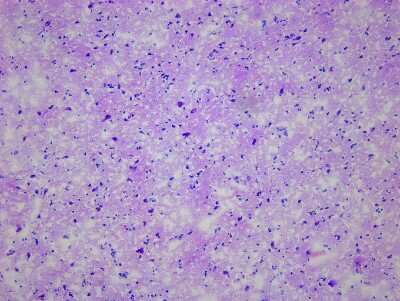

8 results for "Brain Postcentral Gyrus Slides and MicroArrays" in Products

Brain Postcentral Gyrus: Slides and MicroArrays